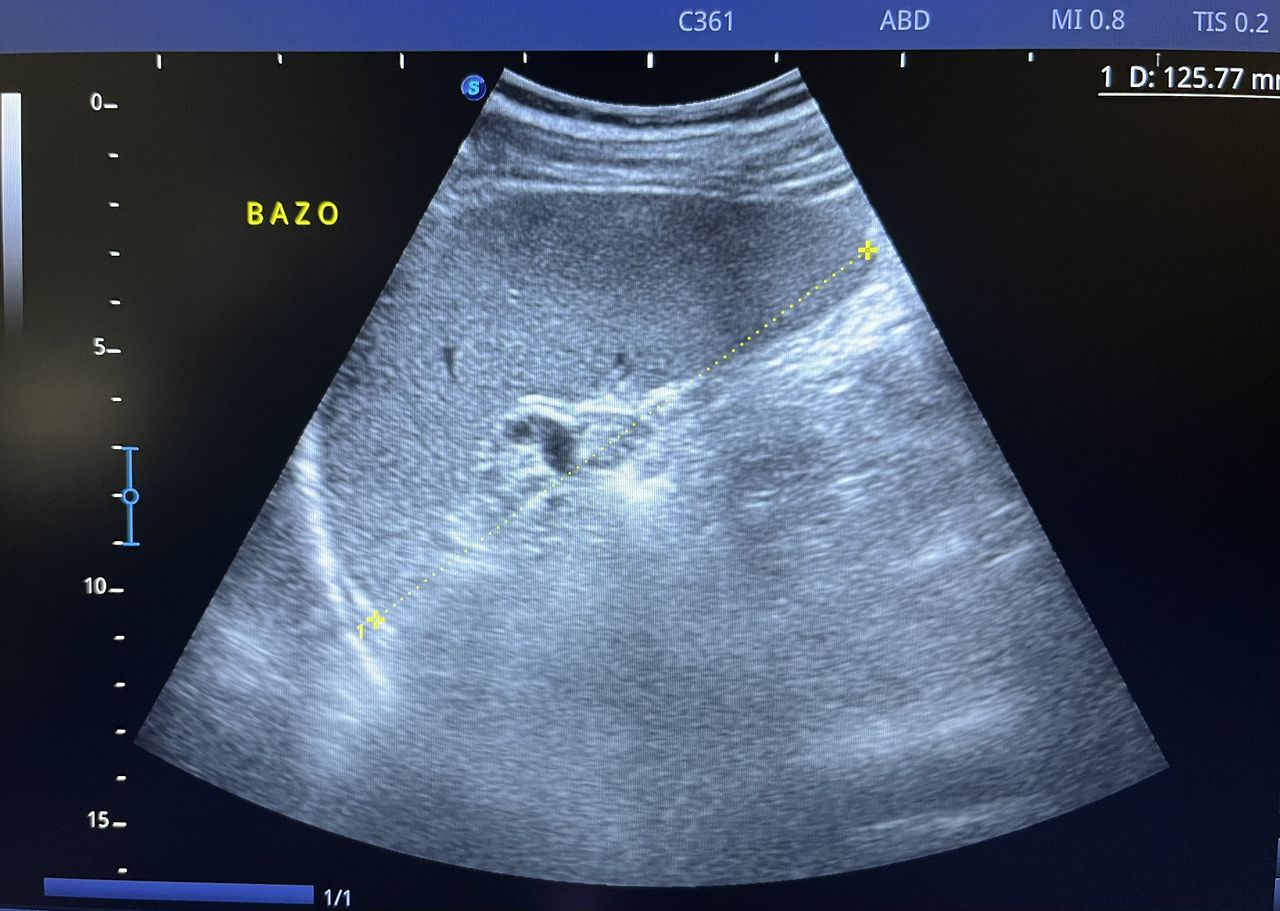

Médico general con 15 años de experiencia, master en enfermedades infecciosas y antibioticoterapia por parte de la Universidad Cardenal Herrera en Valencia, ademas de diversos diplomados en el área de Infectología y Parasitología, Urgencias, Imagenología y Medicina del Trabajo. He laborado en Hospitales y Clínicas en el área de Urgencias, en Laboratorios realizando estudios de Imagen, en especifico ultrasonidos de todo tipo desde básicos hasta avanzados incluidos los obstétricos estructurales, en Secretaría de Salud del Estado de Querétaro realizando ultrasonidos obstétricos para la detección de malformaciones en los tres trimestres del embarazo en diversos centros de salud, como médico de Empresas en el campo de Salud Laboral y actualmente en este consultorio en donde para su mejor atención y siempre buscando integrar la mayoría de las herramientas diagnosticas cuento con equipo de ultrasonido como apoyo en la exploración del paciente o como servicio diagnostico por imagen, realizo ultrasonidos convencionales (hepatobiliar (hígado, páncreas, vesícula y bazo), vías urinarias, ginecológico abdominal y transvaginal, tiroideo, prostático, testicular, pared abdominal) y especializados (dopler obstétrico en los 3 trimestres de embarazo), musculoesquelético en lesiones deportivas. También cuento con un equipo de electrocardiograma de 12 derivaciones para monitoreo completo del funcionamiento cardiaco, espirometria para evaluar la función pulmonar en la consulta, pruebas rápidas que se realizan en consultorio para detectar de forma mas precisa enfermedades infecciosas como Influenza A y B, covid19, infecciones urinarias, dengue, zika, chikungunya. Cuento con diversas vacunas para prevención de enfermedades. Siempre con el objetivo de dar el mejor servicio y atención a su salud. Lo espero en consulta para escucharlo y estudiar su caso de la forma más completa posible, estoy seguro de que tendremos las mejores opciones para su tratamiento. Mi tranquilidad es que usted se vaya con todas sus preguntas e inquietudes resueltas.

• Ultrasonido diagnóstico

• Ultrasonido hepatobiliar

$800